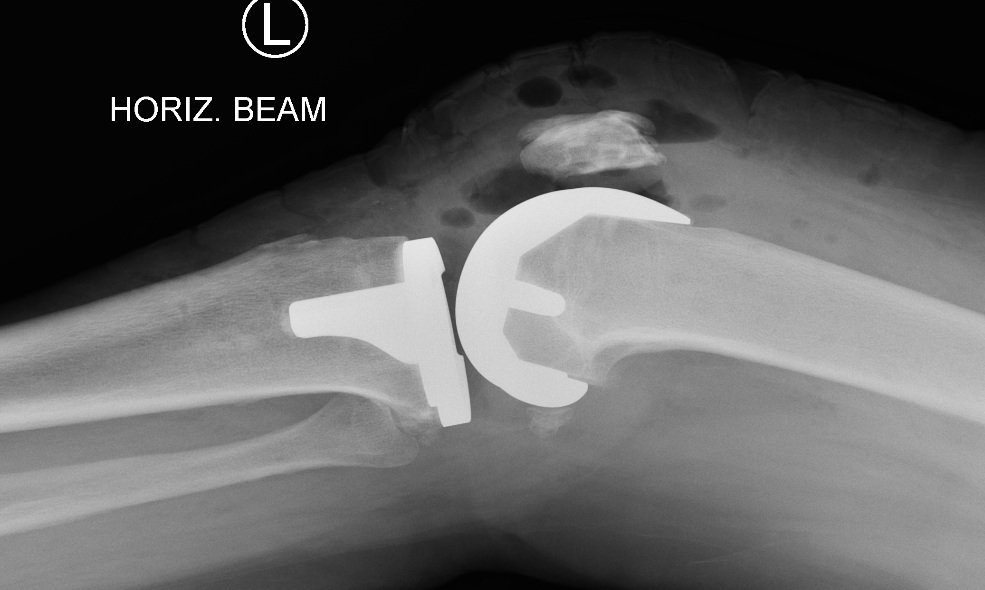

Example of Total Knee Replacement

Side on view of a total knee replacement